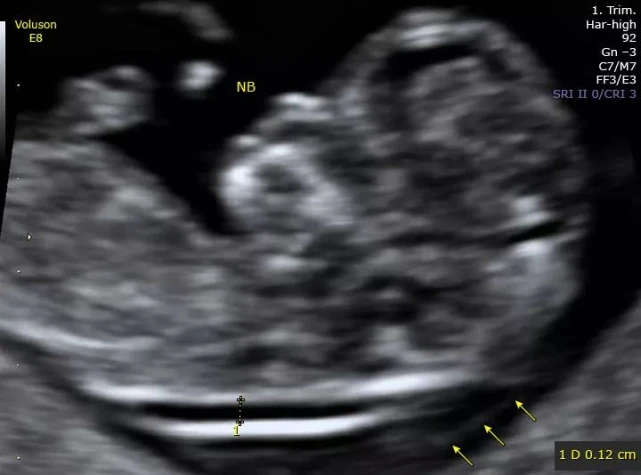

NT检查,又称“颈后透明带扫描“,是通过B超测量胎儿颈项部皮下无回声透明层最厚的部位,是用于评估胎儿是否可能患有唐氏综合征的一种方法。

一般来说,NT正常值在2.5mm以内,NT值高于2.5mm,则提示可能存在染色体异常,NT值越高,胎儿染色体异常的风险越大。同时也存在淋巴系统发育异常、先天性心脏病等疾病的可能。当NT结果异常时,后期孕妈需要进行产前诊断,如羊水穿刺。

胎儿正常NT的超声影像